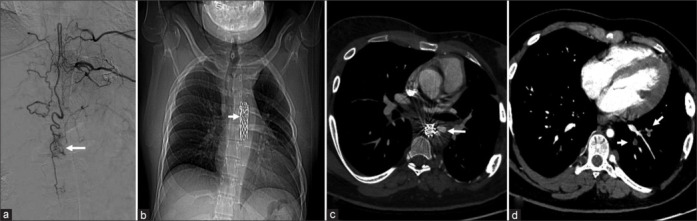

神经纤维瘤病患者在其一生中经历多次手术,对围手术期团队提出了挑战。我们报告一例1型神经纤维瘤病的年轻男性患者,计划在全身麻醉下进行胸椎动静脉畸形的血管内栓塞治疗。相关血管病变包括支架置入的胸降主动脉缩窄,支架远端未修复的囊性主动脉瘤(AA)提示1型内漏,双节段性肺动脉血栓形成,双侧锁骨下动脉狭窄,腹膜后神经纤维瘤压迫腹腔动脉。我们主要关注的是手术过程中可能出现的AA破裂成为外科急诊,血管通路困难,以及围手术期血栓栓塞。通过持续的血流动力学监测,适当的麻醉深度和镇痛,避免术中血流动力学波动。在一次顺利的手术后,患者顺利拔管。对潜在病理生理学的深入了解,对潜在并发症的预测和准备,以及跨学科协调的团队合作有助于保护患者的预后。

Patients with neurofibromatosis undergo multiple surgeries during their lifetime, presenting as challenging scenarios to the perioperative team. We present the case report of a young male patient with type 1 neurofibromatosis scheduled for endovascular embolization of thoracic spinal arteriovenous malformation under general anesthesia. Associated vasculopathy included stented descending thoracic aortic coarctation, an unrepaired saccular aortic aneurysm (AA) distal to the stent suggestive of a type 1 endoleak, bilateral segmental pulmonary arterial thrombosis, bilateral subclavian artery stenosis, and a retroperitoneal neurofibroma compressing the coeliac artery. Our primary concerns were a possible periprocedural AA rupture becoming a surgical emergency, difficult vascular access, and perioperative thromboembolism. Periprocedural hemodynamic surges were avoided using continuous hemodynamic monitoring, adequate anesthetic depth, and analgesia. After an uneventful procedure, the patient was extubated with a smooth postoperative course. An in-depth knowledge about underlying pathophysiology, anticipation and preparedness for potential complications, and interdisciplinary coordinated teamwork serve to preserve patient outcomes.